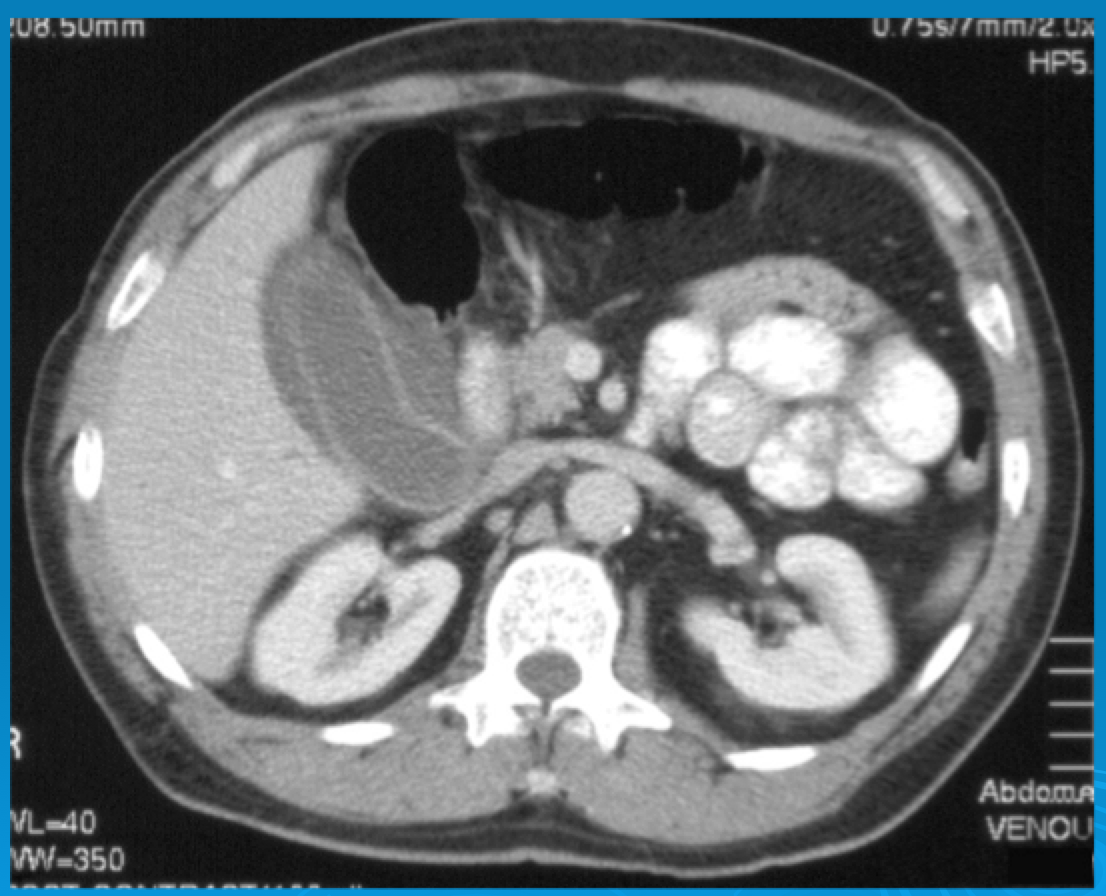

Abdominal CT Scans

HETI (The Health Education Training Institute) provides excellent free educational resources for Emergency Medicine and sponsors conferences for trainees. They have been well known for radiology teaching for several years. Here is a recent resource from the Emergency medicine HETI conference on the Abdominal CT: